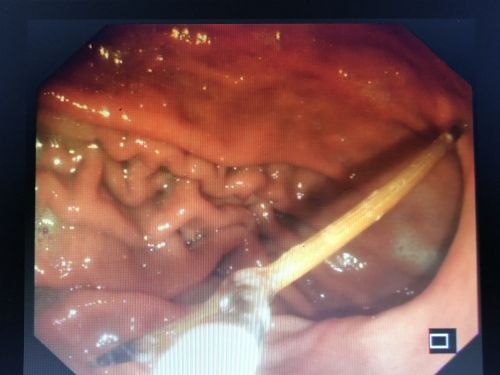

胃镜下取出一根完整的牙签。

听说胃镜下取牙签,不排除出现胃穿孔的情况,家人决定将老人转往长沙的大医院,于是在9月23日住进湖南省人民医院胃肠外科病房。刘祺主任医师与消化内科吴明浩主任医师凭借胆大心细和高超技术,成功在胃镜下取出一根长约6厘米的完整牙签。